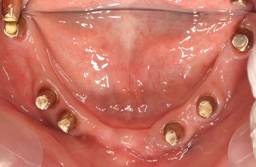

白金加金のアバットメント(土台)

上顎

下顎